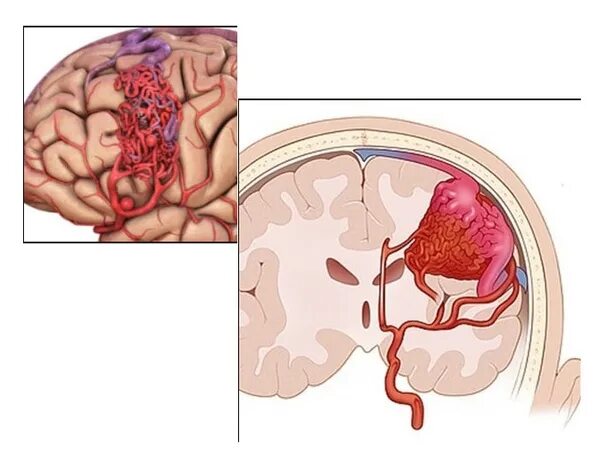

Мальформация сосудов